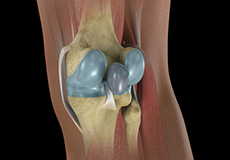

The knee is a hinge joint made up of two bones, the thighbone (femur) and shinbone (tibia). There are two round knobs at the end of the femur called femoral condyles that articulate with the flat surface of the tibia called the tibial plateau. The tibial plateau on the inside of the leg is called the medial tibial plateau and on the outside of the leg, the lateral tibial plateau.

The two femoral condyles form a groove on the front (anterior) side of the knee called the patellofemoral groove. A small bone called the patella sits in this groove and forms the kneecap. It acts as a shield and protects the knee joint from direct trauma.

Movement of the bones causes friction between the articulating surfaces. To reduce this friction, all articulating surfaces involved in the movement are covered with a white, shiny, slippery layer called articular cartilage. The articulating surface of the femoral condyles, tibial plateaus and the back of the patella are covered with this cartilage. The cartilage provides a smooth surface that facilitates easy movement.

Within the knee joint, between the femur and tibia, are two C-shaped cartilaginous structures called menisci. Menisci function to provide stability to the knee by spreading the weight of the upper body across the whole surface of the tibial plateau. The menisci help in load-bearing i.e. it prevents the weight from concentrating onto a small area, which could damage the articular cartilage. The menisci also act as a cushion between the femur and tibia by absorbing the shock produced by activities such as walking, running and jumping.